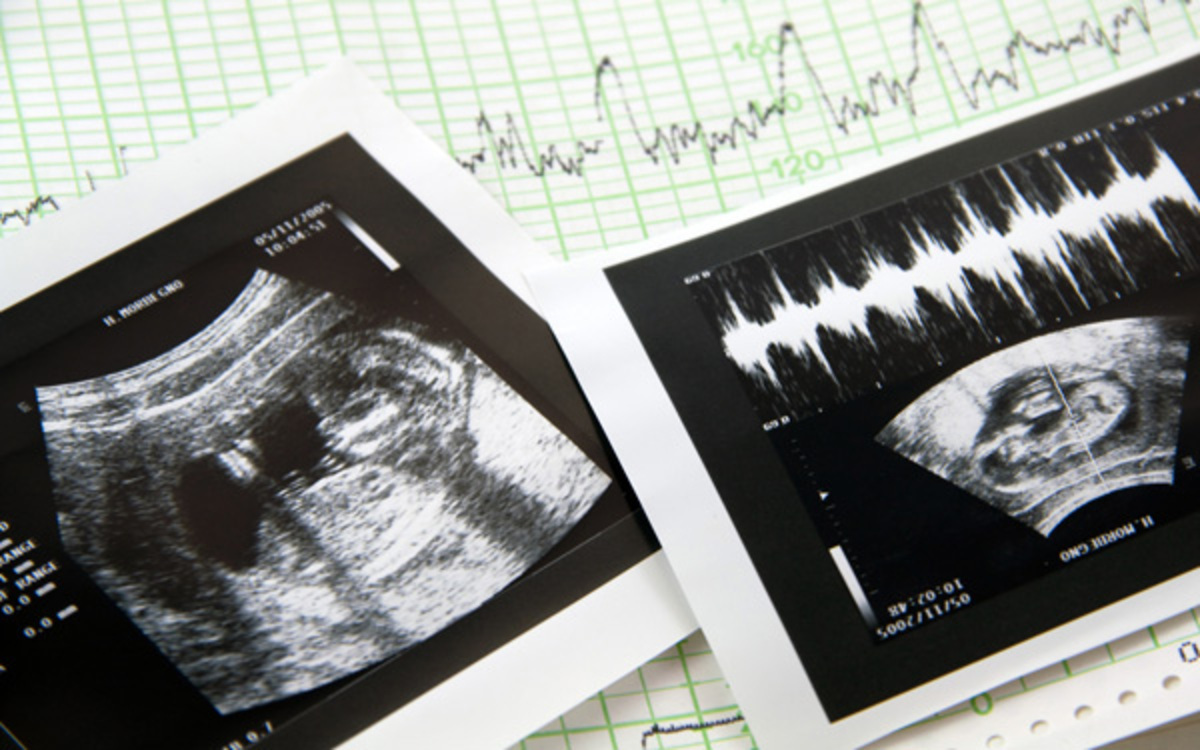

8月 エコー. 母体のエネルギー配分が変わり、甘いものが欲しくなる 妊娠28週、妊娠8ヶ月になると、胎児の体がぐんぐん成長。 母体の脂肪からつくられるブドウ糖が、優先的に送られるようになります。 これが「母体のエネルギー配分が変わる」ということ。 体内のブドウ糖がどんどん胎児に運ばれてしまうので、ママはケーキやチョコレート、アイスクリームなどを欲する. 妊娠8ヶ月(妊娠28週~妊娠31週)のエコー写真 ©ママリ 妊娠8ヶ月はおなかの赤ちゃんは40cmを超え、体重も1,500gを超えてくる時期です。赤ちゃんはほとんどの器官が完成に近づき、目の網膜が完成することで明るさを感じることができるようになります。 ©マ. 妊娠8ヶ月のエコーでダウン症と分かる? ダウン症は、エコーでダウン症の可能性が あるかもしれないという あくまで疑いのレベルでわかることがあります。 妊娠初期では、首に浮腫が見つかったり、 後期には手足が短い、という特徴が.

赤ちゃんの超音波、エコー写真。妊娠週ごとに掲載されているので、あなたのエコー写真と比べてみては? 2d、3d、カラー超音波など種類もさまざまですね。(エコー写真の保存) 妊娠中のエコー写真 見たい妊娠月にジャンプ↓. チャンネル登録お願いします!http//wwwyoutubecom/tometomoka?sub_confirmation=1 #妊婦 #4Dエコー #妊娠8ヶ月 ボディペイント. こんにちは、ばななつまです。 妊娠6ヶ月から切迫早産と妊娠糖尿病のダブルパンチで週に一回通院しています。 そんなわたし、ついに妊娠8ヶ月、妊娠後期に突入したぞ〜!!! 28週妊婦健診 検尿→問題なし 腹部エコー→赤ちゃん推定体重1,196g! 大きさ順調、心臓元気。.